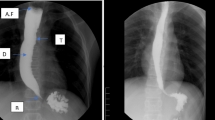

Schima, W. et al. Globus sensation: value of static radiography combined with videofluoroscopy of the pharynx and oesophagus. Clin. Radiol. 51, 177–185 (1996).

Caylakli, F., Yavuz, H., Erkan, A. N., Ozer, C. & Ozluoglu, L. N. Evaluation of patients with globus pharyngeus with barium swallow pharyngoesophagography. Laryngoscope 116, 37–39 (2006).